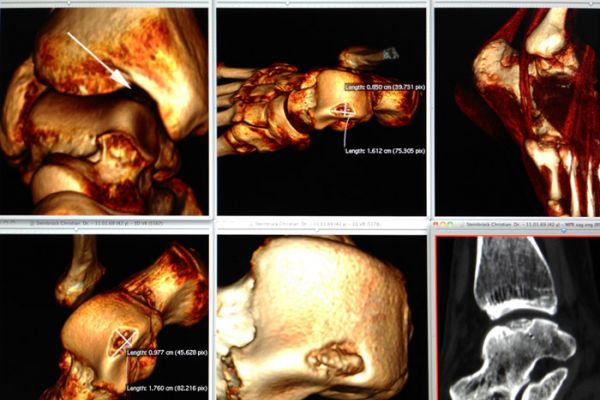

Die Computertomographie ist ein Röntgenverfahren, welches Schnittbilder des menschlichen Körpers erzeugt.

Der Patient liegt auf einer speziellen Untersuchungsliege und wird langsam durch den Detektorring gefahren. Die Röntgenröhre rotiert dabei spiralförmig um einen definierten Körperabschnitt um den Patienten , wobei ein kontinuierlicher Datenblock erzeugt wird mit der Möglichkeit, durch Nachbearbeitung (Rekonstruktionen) Schichtbilder in verschiedenen Ebenen und Schichtdicken, oder ein 3D-Modell der untersuchten Organe (z.B. Knochen, Gefäße) zu erstellen.